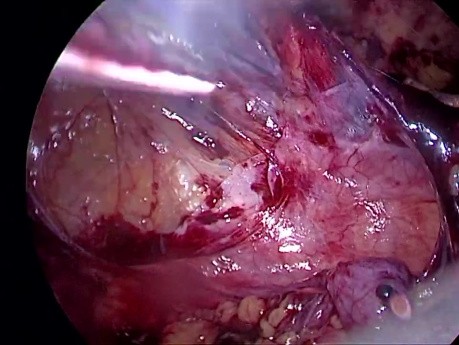

Tratamiento laparoscópico TEP de la hernia inguinal...

Tratamiento laparoscópico TEP de hernia inguinal derecha.